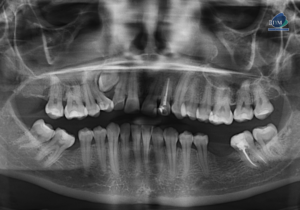

Caso 300 – IDM – HIPERPLASIA DE APÓFISIS CORONOIDES DE LADO DERECHO – IDM

Paciente femenino de 16 años acude al Instituto de Diagnóstico Maxilofacial (sede Miraflores) para evaluación quirúrgica. Radiografia Panorámica A la evaluación de la radiografía panorámica